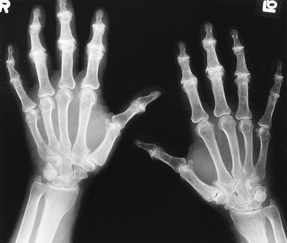

Heberden’s nodes- From operation-pro.de

Although osteoarthritic joints can be warm and swollen, there is usually less swelling in osteoarthritis than some other forms of arthritis like rheumatoid arthritis or gout.

Osteoarthritis can lead to joint deformity. Sometimes the two bones in a joint actually fuse and the joint loses its

flexibility. As the body attempts to repair the damage joints, extra bone may form around the joint causing the joint to get larger and sometimes have “bumps”. These bumps are otherwise known as Heberden’s and Bouchard’s nodes.

X-Rays

In more advanced osteoarthritis, xrays can show narrowing of the space between two bones and even joint damage characteristic of osteoarthritis.